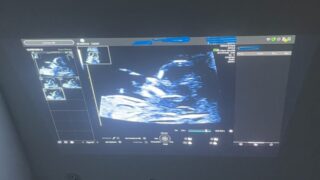

NSTで異常発生!急遽出産することに!

こんにちは!諸々と時系列が前後してしまっていますが、本日は出産のお話です。遂に35週から妊婦健診の間隔が毎週に....!...